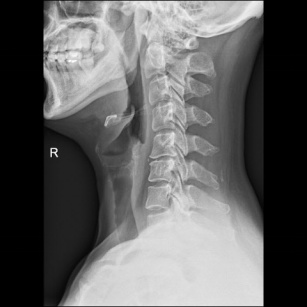

术前X片

术前CT 术前MRI